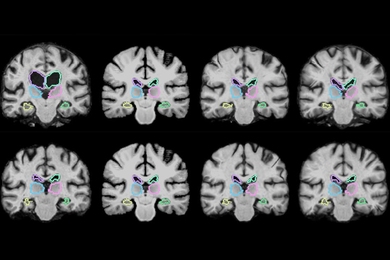

In an article for Forbes about how AI could improve healthcare, Bernard Marr highlights an algorithm developed by MIT researchers that can analyze 3-D scans up to 1,000 times faster than is currently possible. “When saving minutes can mean saving lives, AI and machine learning can be transformative,” writes Marr.